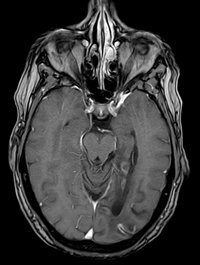

Posteriorinfarkt

Posteriorinfarkt T1 mit KM - axial